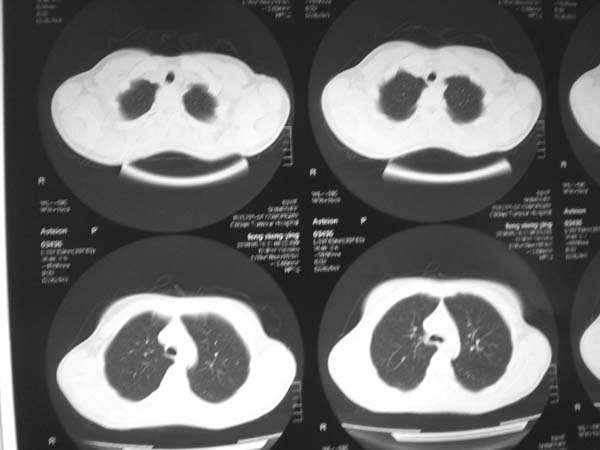

标题: CT13486:F 17Y 咳嗽 咳痰数日请会诊 [打印本页]

标题: CT13486:F 17Y 咳嗽 咳痰数日请会诊

白细胞9600不发烧

考虑右下结核球

右肺下叶结核灶

右下肺背段病灶,考虑结核与炎症鉴别,请进一步检查.

考虑为:右肺下叶外基底段结核球。

结果;痰中找到结核杆菌

痰涂片已找到结核杆菌  将结果告诉大家